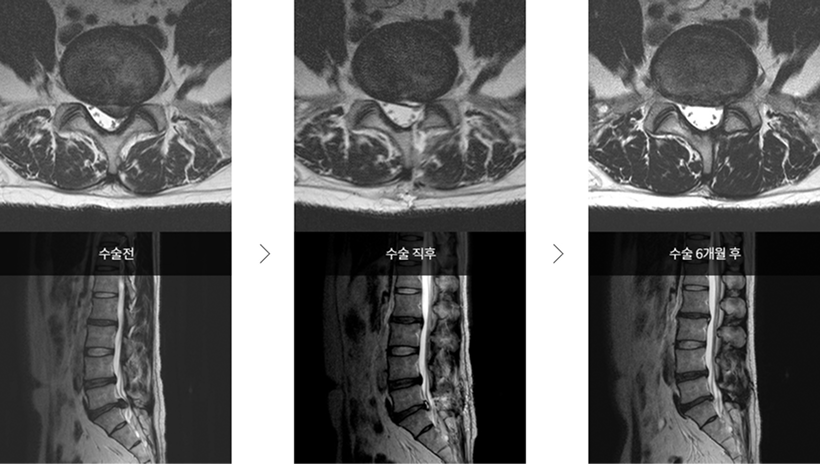

미세현미경수술 시술 사례 미세현미경수술 시술 사례

▲ 척추관 협착증

미세현미경수술 시술 사례